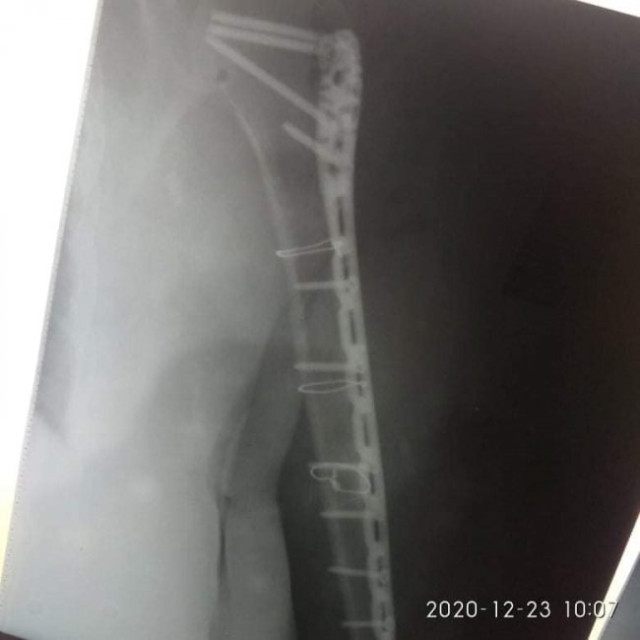

21 грудня їй провели 4-ьох годинну операцію – остеометалосинтез правої плечової кістки за допомогою LCP проксимальної Philos пластини та гвинтів.

Операція пройшла у складі лікарів-травматологів: Лотоцького І.А., Радчука В.М, Босого Т.Б..